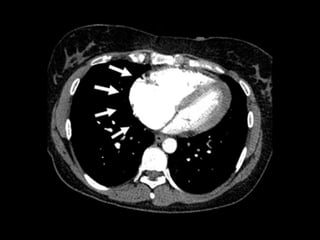

• #62 Spiral-CT des Thorax nach intravenöser Kontrastmittelgabe. Pneumomediastinum (Pfeil) und linksseitiger Pleuraerguss (*)